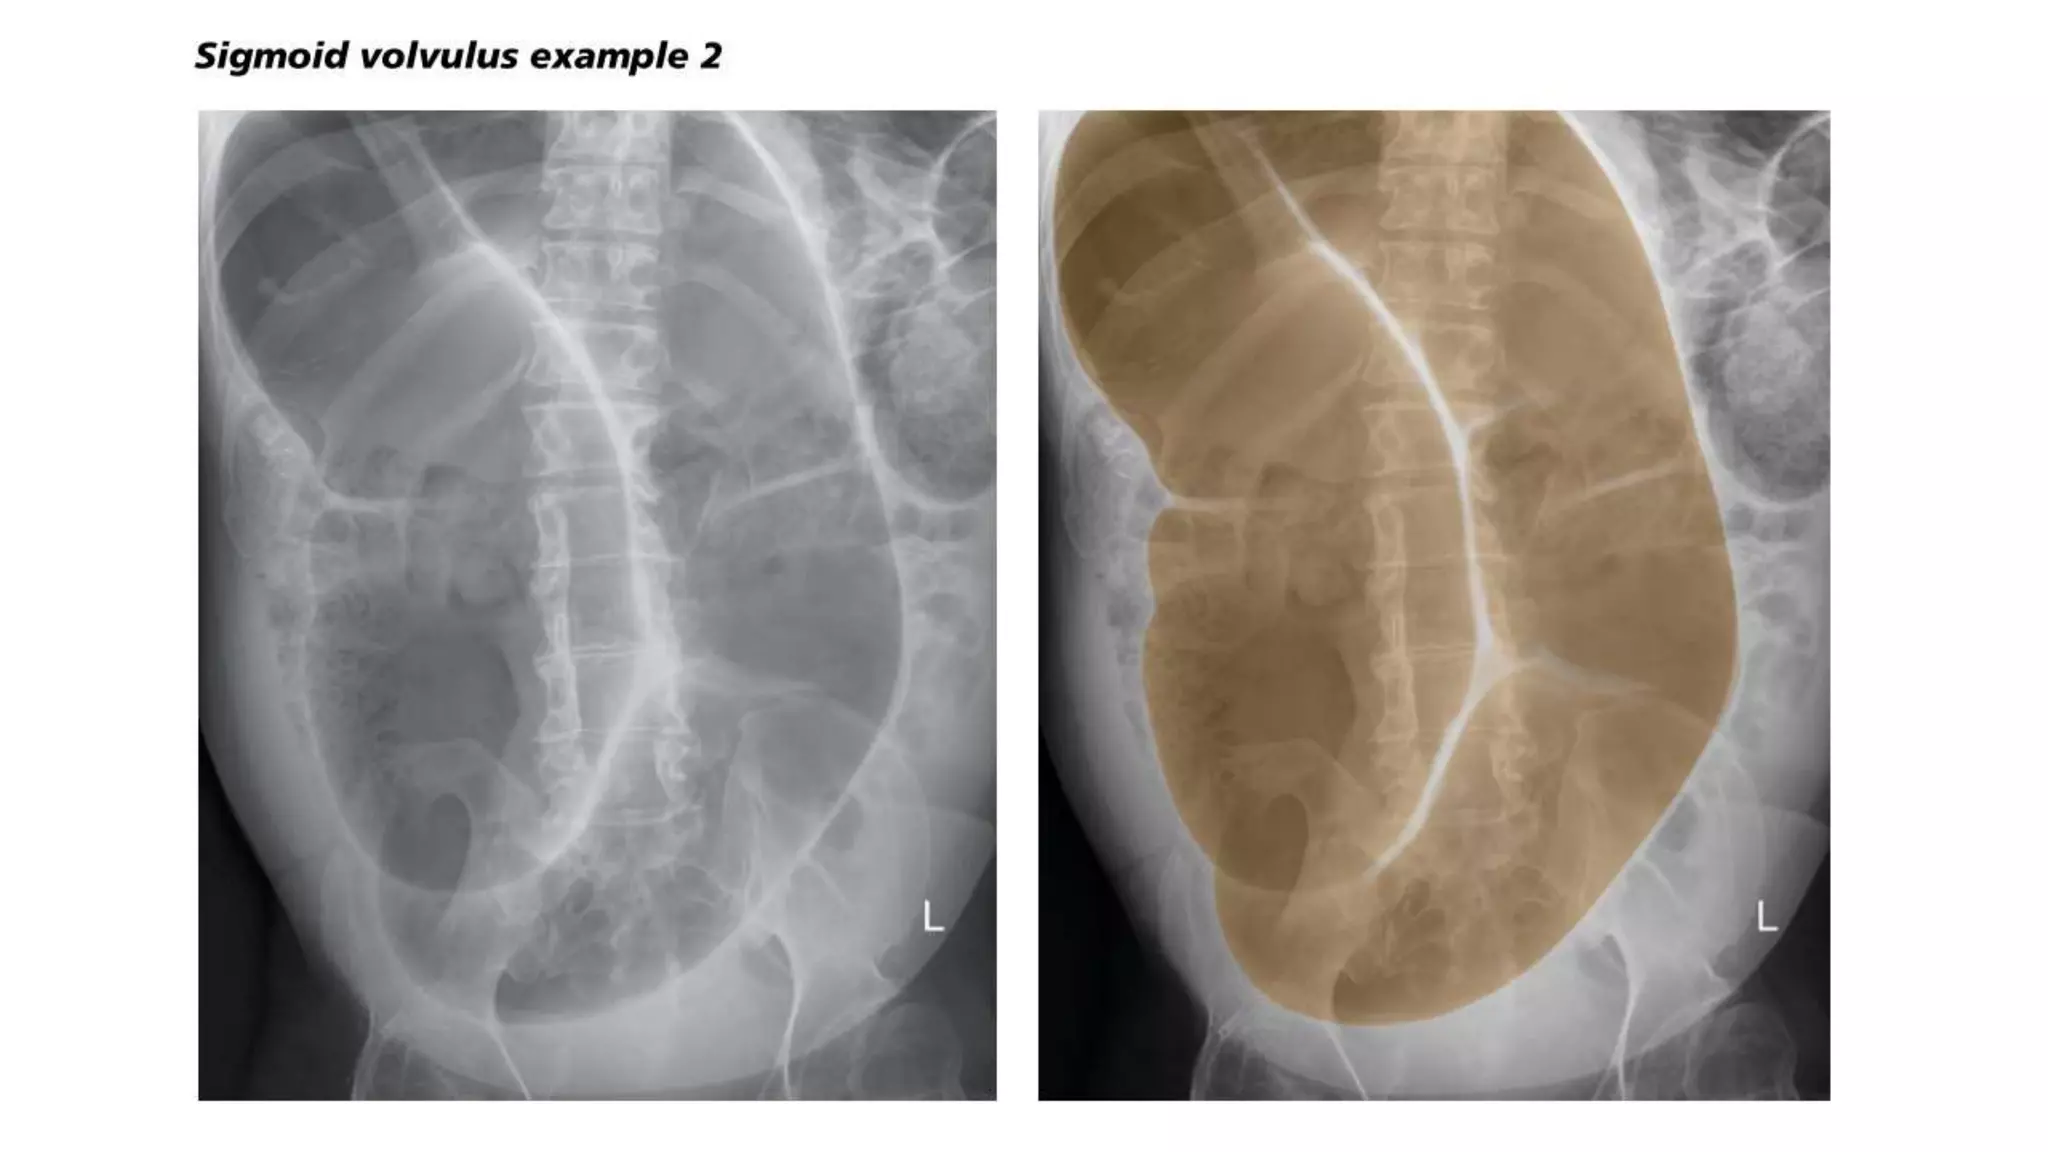

Sigmoid volvulus, Management

• The goal of treatment of sigmoid volvulus is to reduce the sigmoid volvulus

and to prevent recurrent episodes.

• We perform a flexible sigmoidoscopy to reduce a sigmoid volvulus and then

perform definitive surgery to prevent recurrent volvulus.

• We perform immediate laparotomy when endoscopic detorsion is unsuccessful

or in patients with signs and symptoms suggestive of peritonitis.

• However, the management of sigmoid volvulus is controversial. Some experts

recommend that endoscopy be reserved for patients who are not candidates

for definitive surgical therapy, while others recommend surgery be reserved for

patients in whom sigmoidoscopic reduction is unsuccessful since approximately

40 to 50 percent of patients with sigmoid volvulus will not have a recurrence.